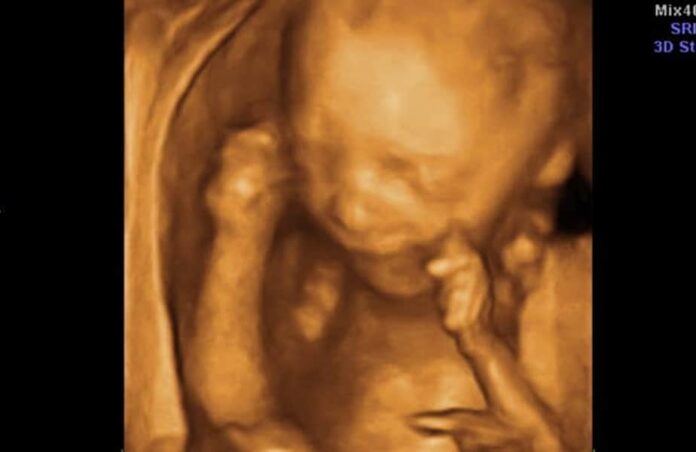

La Iniciativa 120 prohibiría el aborto en Colorado después de 22 semanas de embarazo, con la excepción de que la vida de la madre esté en riesgo. Según una encuesta reciente de Gallup, el 74 por ciento de los estadounidenses creen que debería haber limitaciones para el aborto tardío. La organización Due Date Too Late originalmente presentó las firmas recaudadas el pasado 15 de marzo, pero se quedó corta por 10,000 después de la revisión estatal. El “periodo de subsanación” comenzó el 15 de mayo con la meta de recaudar al menos 10,000 firmas válidas de votantes registrados en Colorado durante un periodo de 15 días para alcanzar el límite de 124,632 y calificar para la boleta electoral de noviembre.